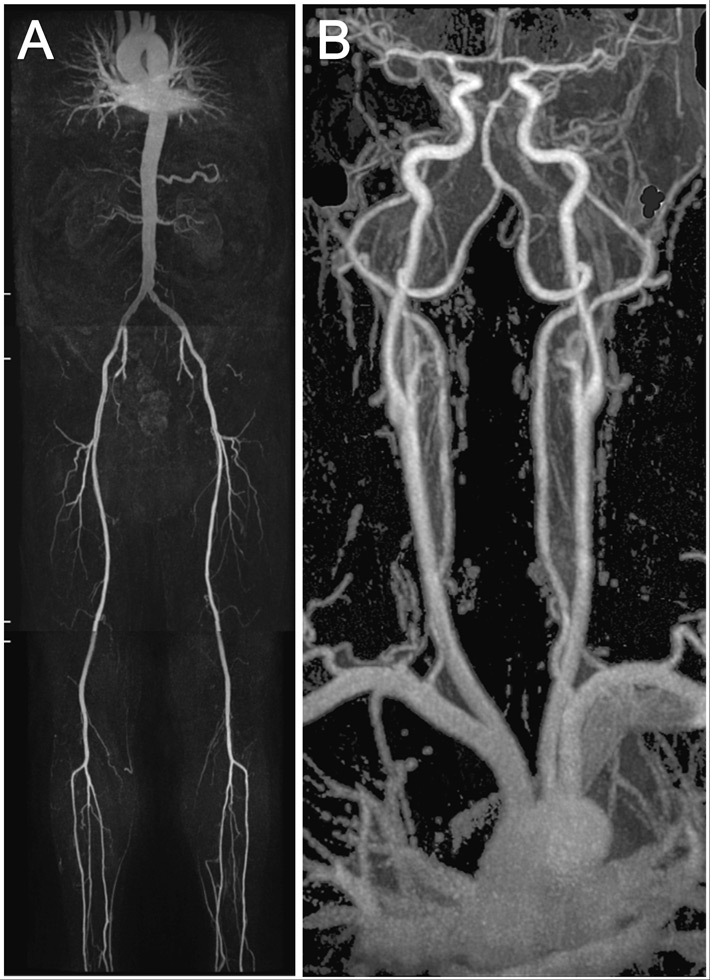

Figure 1

An example showing the MR whole body angiography.

The first part of the MR whole body angiography included thoracic/renal-, pelvis/thigh-, knee/calf-stations (A). The second part included the thoracic/carotid-station (B).

All MR angiography (MRA) examinations were performed on a 1.5-T whole-body MR system (Philips Achieva, Release 2.6, Philips Healthcare, Best, the Netherlands) with a gradient strength of 30 mT/m and a slew rate of 150 (mT/m/msec) according to previously described protocols [7, 8]. The scanning protocol involved a 2 step approach. The first part of the examination was in feet first, supine position, for the renal arteries down to the calf arteries with automatic table movement between the stations, using a 12-element phased-array peripheral vascular coil (Philips Healthcare). A biphasic intravenous administration of gadobenate dimeglumine with 0.15 mmol per kilogram of body weight at flow rates of 2.0 ml/sec followed by 0.033 mmol per kilogram of body weight at flow rates of 0.9 ml/sec, followed by a 30 mL saline flush at a flow rate of 0.8 ml/sec (fig. 1A). In the second part of the examination a 16 -element phased-array Neurovascular coil (Philips Healthcare) was used for the carotid and thoracic arteries in head first and supine position. An intravenous administration of gadobenate dimeglumine with 0.15 mmol per kilogram of body weight at flow rates of 1.5 ml/sec followed by a 30 ml saline flush at a flow rate of 1.5 ml/sec (fig. 1B).